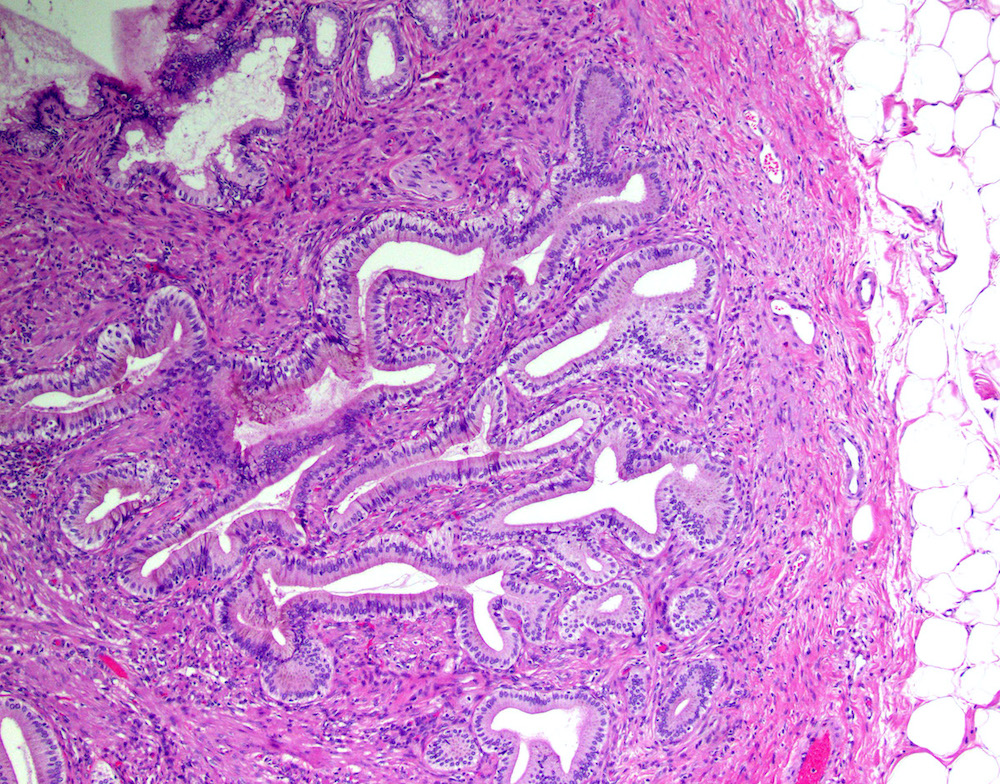

Microscopic (histologic) description

- Cystically dilated benign biliary glands accompanied by smooth muscle hypertrophy of gallbladder wall, thickened / fibrotic subserosa (StatPearls: Adenomyomatosis [Accessed 26 January 2021])

- Glands are distinct from the Rokitansky-Aschoff sinuses, which are epithelial diverticula, usually multifocal and occur throughout gallbladder secondary to injury, versus adenomyomatous nodule (distinct localized lesion of the gallbladder wall, 1 - 1.5 cm mural nodule in the fundus) (Am J Surg Pathol 2020;44:1649)

- May have reactive epithelial changes, papillary change and intestinal metaplasia (StatPearls: Adenomyomatosis [Accessed 26 January 2021])

Microscopic (histologic) images

Contributed by Monica T. Garcia-Buitrago, M.D.